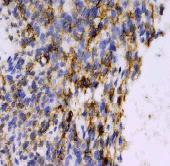

Immunohistochemistry (Formalin/PFA-fixed paraffin-embedded sections) - Anti-CD99 antibody [EPR3097Y] (AB75858)

Immunohistochemistry (Formalin/PFA-fixed paraffin-embedded sections) analysis of human prostatic hyperplasia tissue sections labeling CD99 with Purified ab75858 at 1 : 1000 dilution (0.14 µg/ml). Heat mediated antigen retrieval using Bond™ Epitope Retrieval Solution 2 (pH 9.0). Rabbit specific IHC polymer detection kit HRP/DAB (ab209101) was used for detection. Negative control : PBS instead of the primary antibody. Hematoxylin was used as a counterstain.